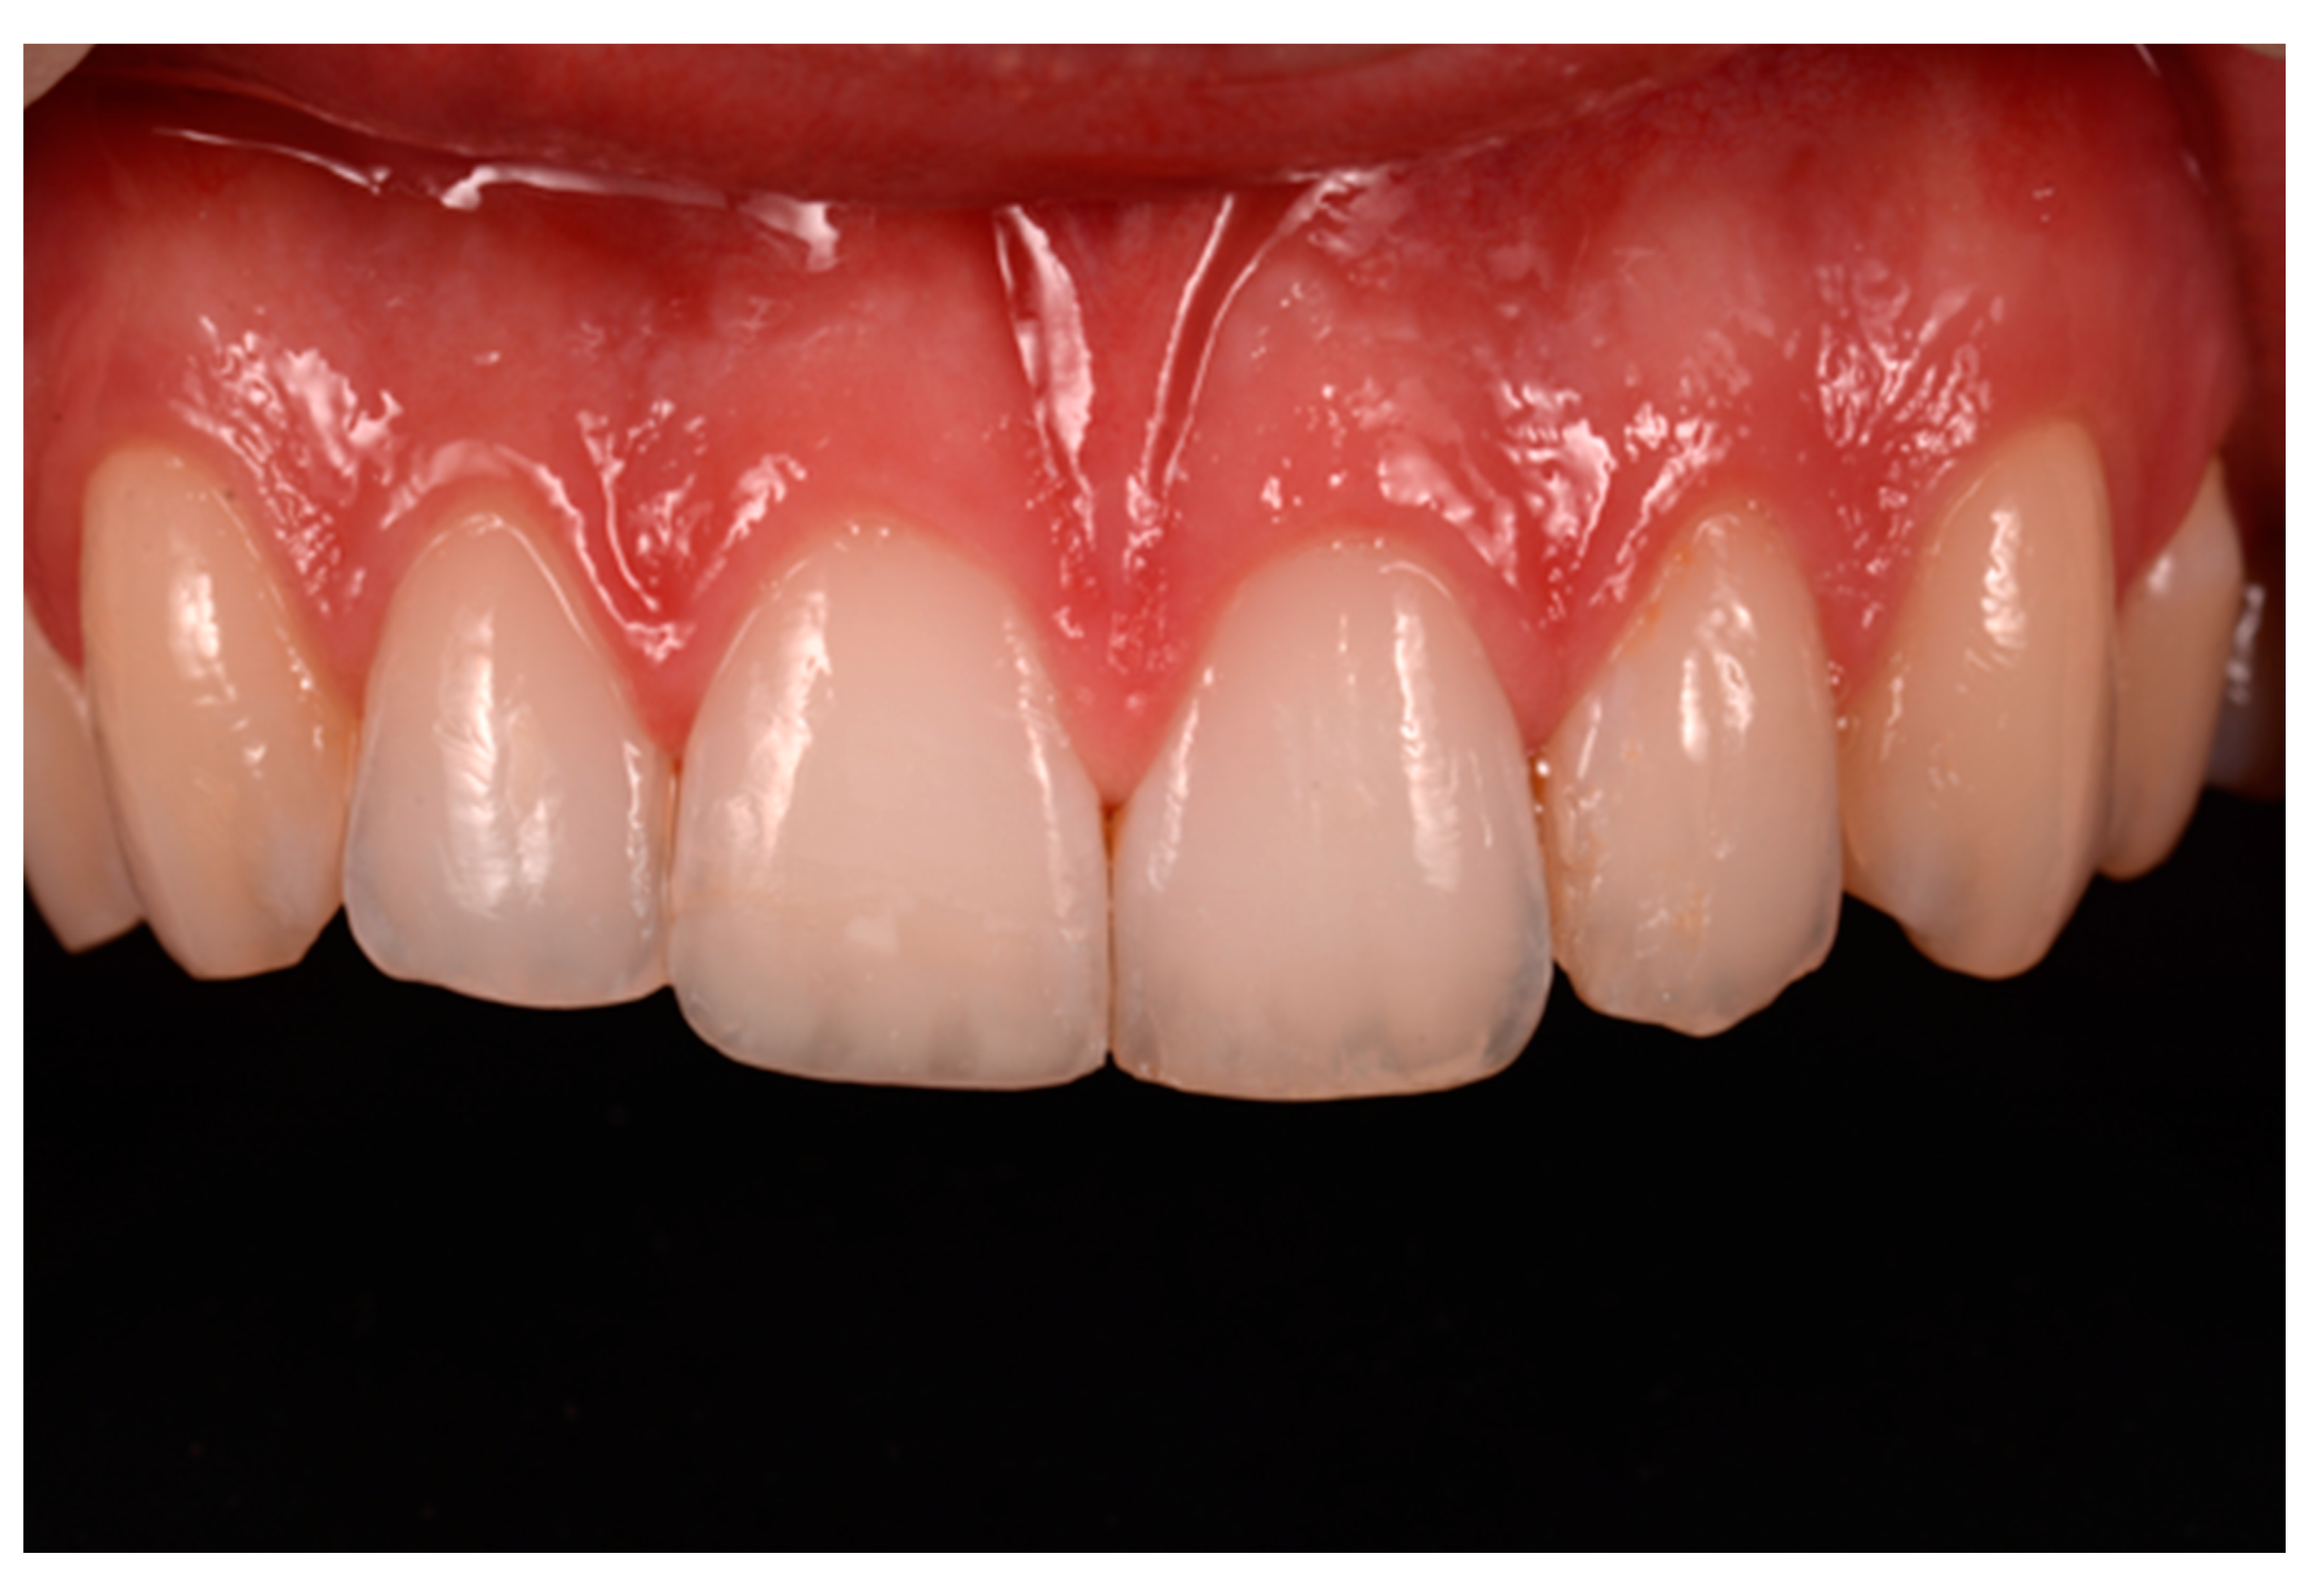

A 27-years lady presented to the dental office after traumatic accident (Figure 30). Tooth #1.1 responded positively to pulp tests (cold and electrical) while Tooth #2.1 showed pulp exposure and continuous bleeding. Endodontic treatment was therefore performed on #2.1 (Figure 31) and direct restoration of both teeth was planned. Shade was selected as described in previous case, using the button-try technique [14]. Even in this clinical case, considered the sufficient ferrule, no post was applied on Tooth #2.1. After isolation and preparation (Figure 32), adhesive procedures were performed using a self-etch two-step adhesive with selective etching procedure (Clearfil SE, Kuraray Noritake Dental, Tokyo, Japan).

Once completed, the two frames (Clearfil Majesty ES-2, A1E, A2D, Kuraray Noritake Dental, Tokyo, Japan) showed internal and external excesses that were reduced using diamond burs and discs (Figure 33 and Figure 34) strictly following the procedure described in Section 2.1.2 of present article. Excesses were removed from the distal-incisal angle of #2.1 allowing therefore to obtain the desired translucency. After silane application and bonding procedure (Figure 35) as described in Section 2.1.2, restorations were completed (Figure 36 and Figure 37). They both show satisfactory clinical integration 1.5 years post-operative (Figure 38 and Figure 39).

Figure 38.

At 1.5 years, post-operative clinical view. Reprinted from Restauri diretti nei settori anteriori, G. Paolone, S. Scolavino, © 2021, with permission from Quintessence Publishing Italy.